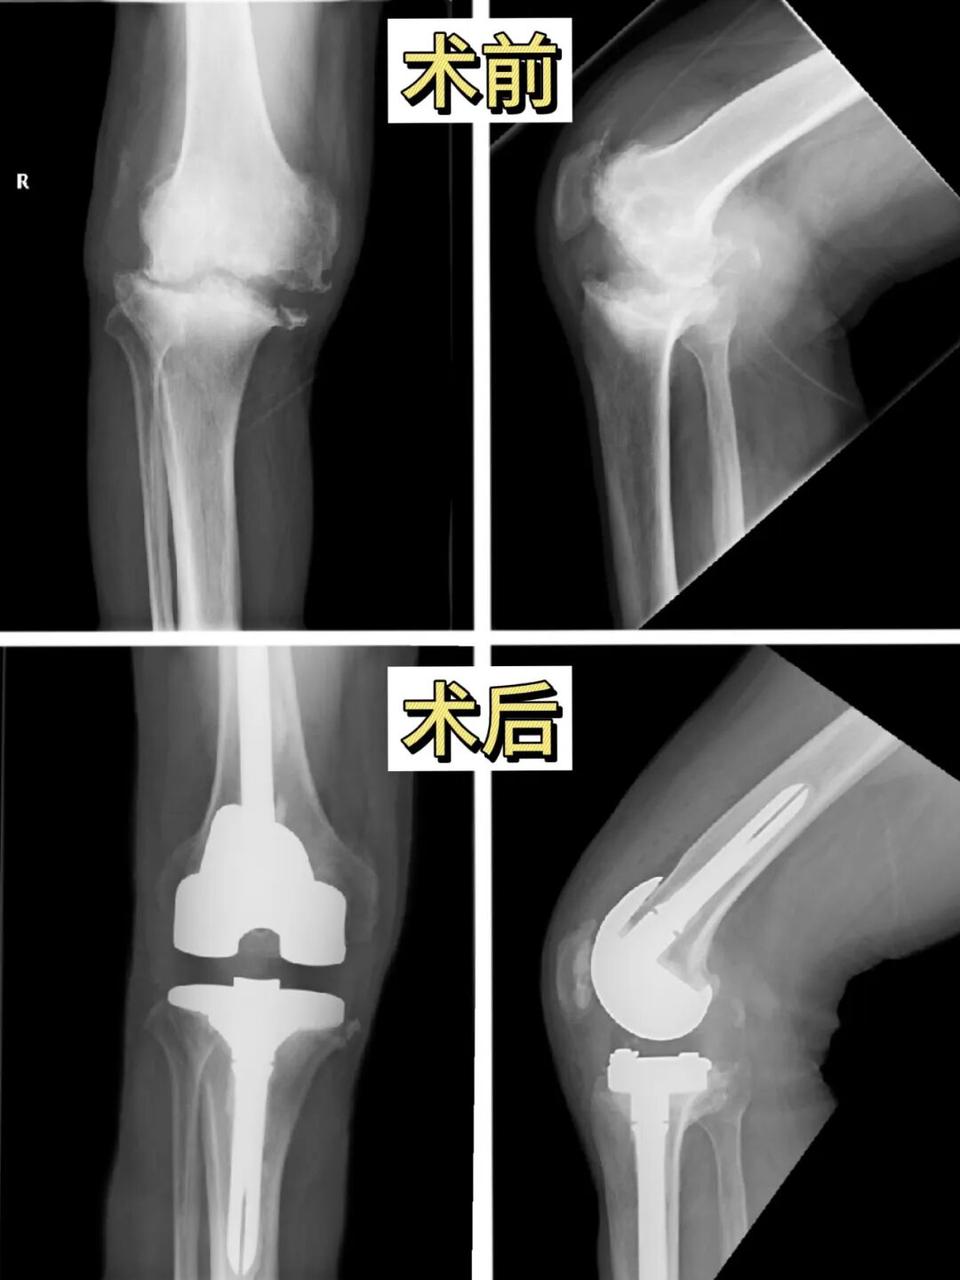

不到四个月,成功开展100余例膝关节置换手术。

这是宏信健康骨科首席专家李军教授带领邳州东大医院骨科团队交出的最新成绩单,其中包含多例严重屈曲挛缩畸形等复杂病例。

· 复杂病例承接能力提升:膝关节屈曲挛缩是中重度畸形的代表术式,对软组织松解、屈伸间隙平衡技术要求较高,过去在县级医院开展较少,反映团队具备了处理复杂病例的技术储备。

随着诊疗能力的提升,周边县市患者纷纷慕名前来就诊。近期,更有河南患者专程前往邳州东大医院接受CCK人工假体膝关节置换手术。